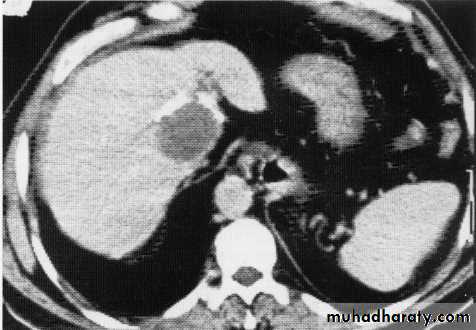

hepatic mets

hepatic mets,arterial phase

hepatic mets venous phase